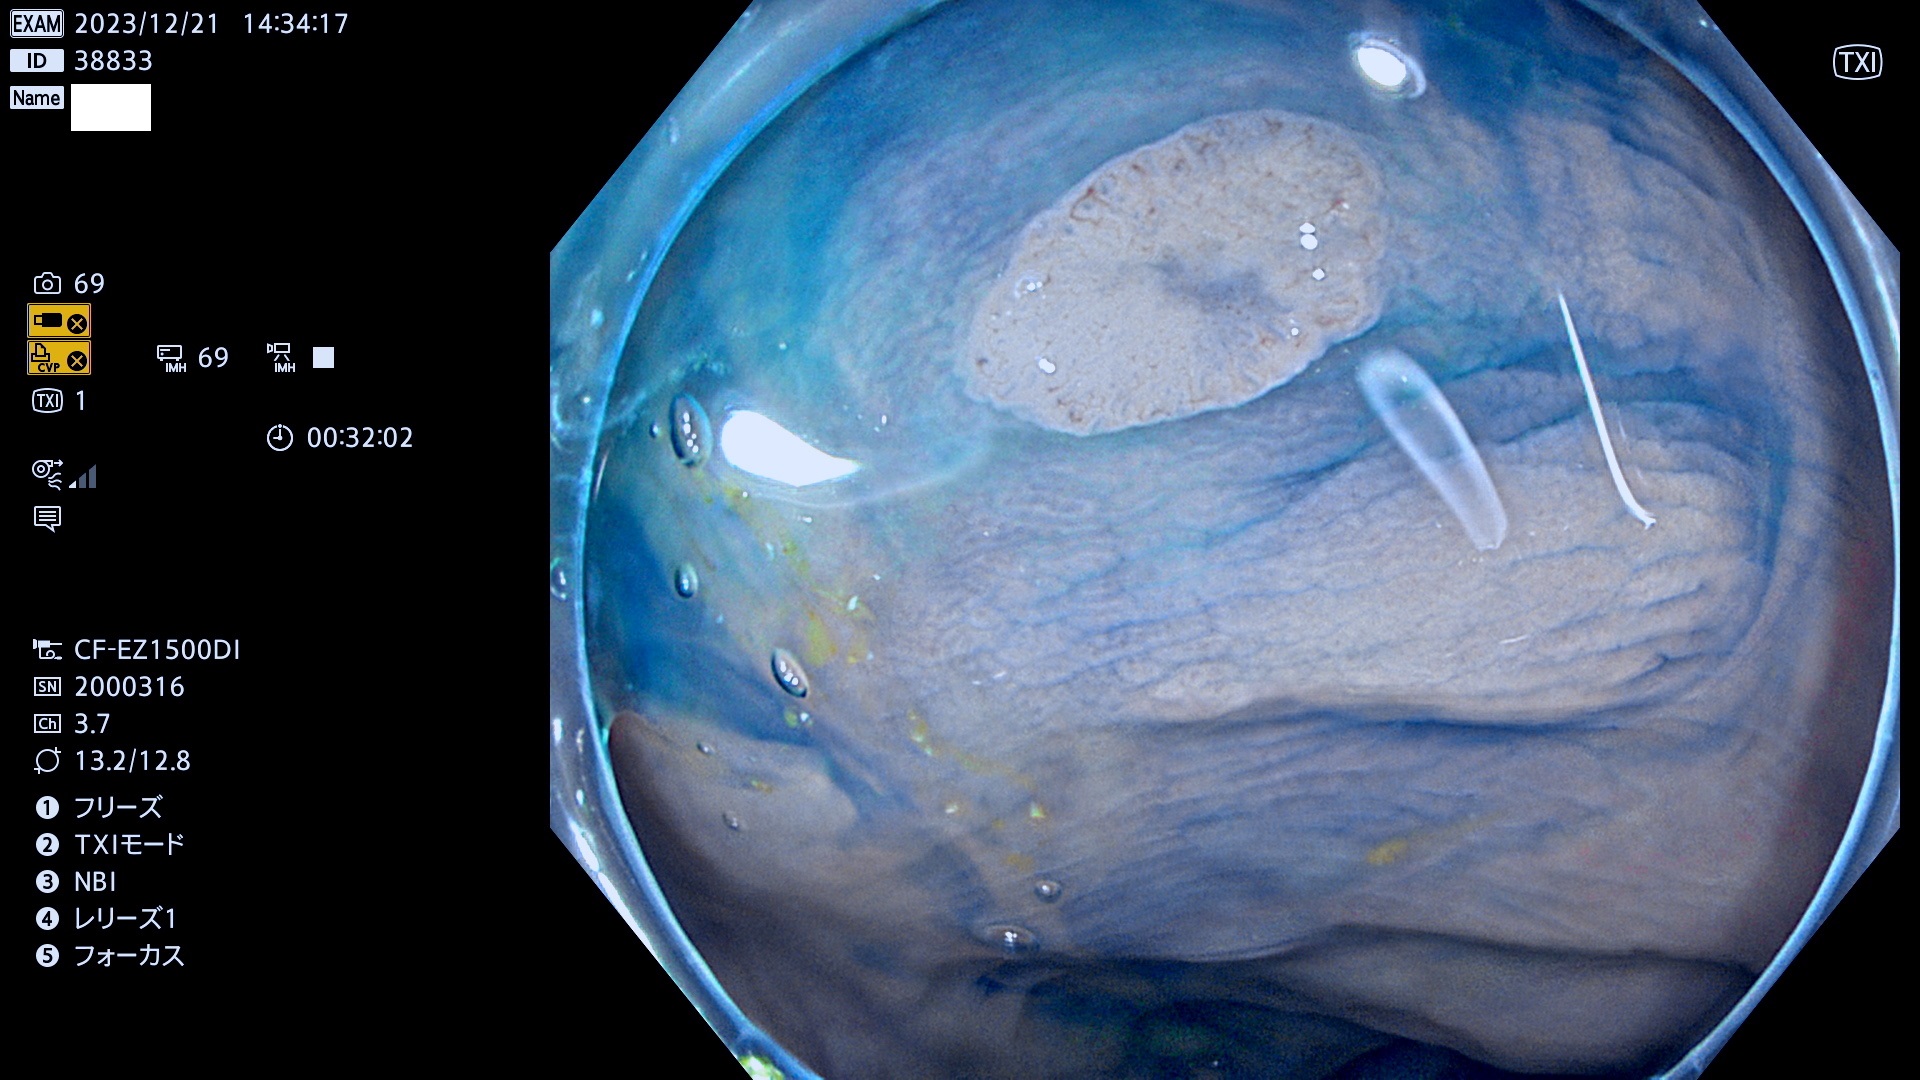

表面型腺腫(Flat Adenoma)の中で、完全に平坦な物をUb、陥凹している物をUcと呼びます。平坦隆起型(Ua)よりも、発見が難しく危険な病変です。

抽出の対象期間 2023年12月21日(木)〜12月24(日)の4日間(48件の検査)6件

当院で見つかった、炎症(ビラン)と極めて紛らわしい腺腫の例